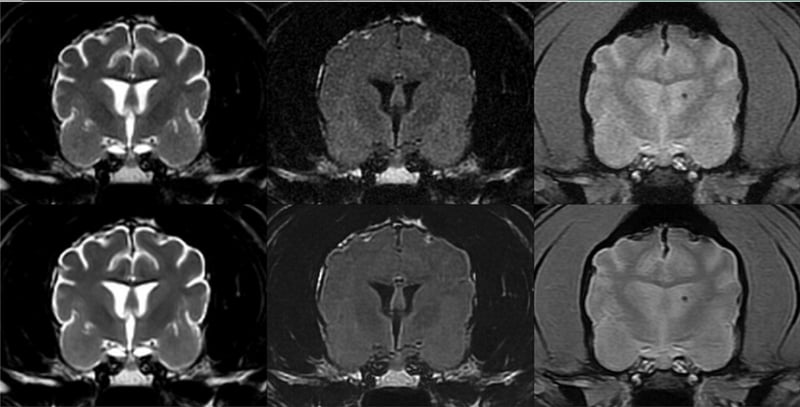

Vet Radiol Ultrasound. 2025